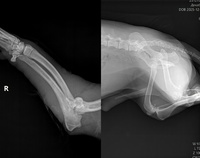

Сейчас Егорка чувствует себя хорошо! Он отогрелся не только физически, но и душой — стал добрее и начал доверять людям, что очень важно при его «деловом» характеретНа общем консилиуме было принято решение обойтись без операции. И уже есть небольшой прогресс: лапка постепенно заживает, появилась минимальная опора. Скорее всего, хромота останется с Егоркой навсегда, но это не критично для его здоровья и жизни. Эта особенность, которая не помешает ему быть самым счастливым псом на свете в любящей семье.тДавайте вместе пожелаем Егорке скорейшего восстановления и самое главное - обрести свой дом с ответственным хозяином! Приглашаем вас в гости в Приют для бездомных животных г. Первоуральск знакомиться с Егоркой! Забирайте его домой, ведь дома и стены лечат!8-922-600-10-21